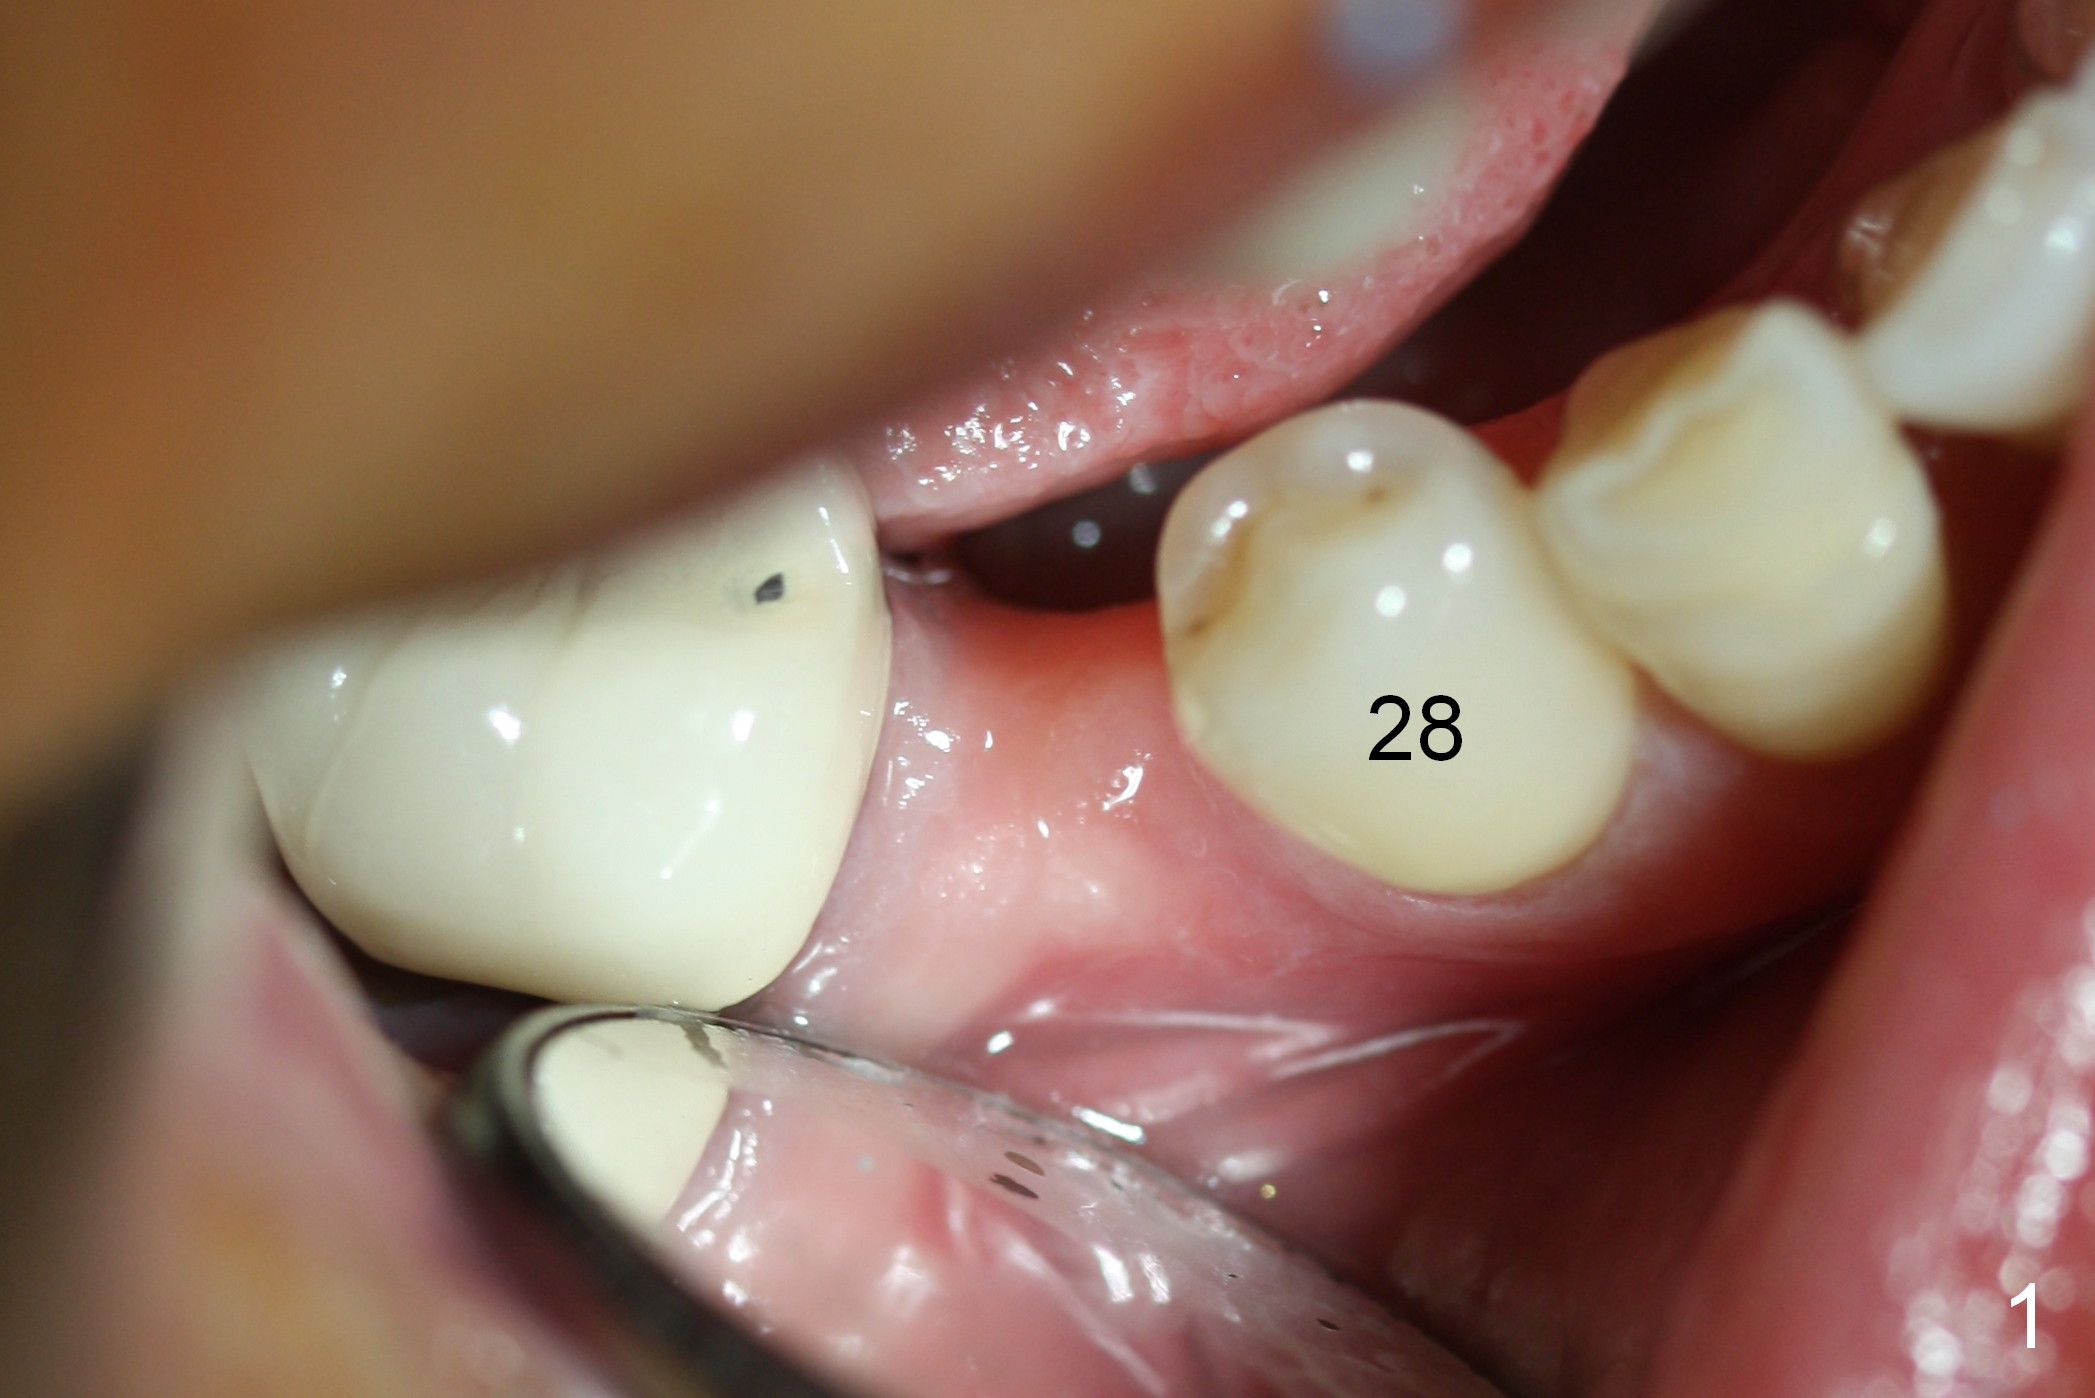

Preop photo shows the distal inclination of the tooth #28 (Fig.1).  The distal surface of the latter is reduced before incision for implant placement at #29 (Fig.2).  The buccolingual width is approximately 4 mm, as compared to 3 mm implant positioner (Fig.3).  After 1.2x10 mm osteotomy (Fig.5), the mesiodistal cortical bone is removed with a small high-speed fissural bur (Fig.4).  When a 2.5x12(2) mm 1-piece implant is placed (Fig.6), there is no buccal (Fig.7) or lingual plate perforation.  There is no postop paresthesia.  There is mild bone loss distal 4 months postop (Fig.8 *).  Take photos before and after permanent crown cementation to show increase in ridge width after bone graft and improvement in gingival health after provisional modification.  Take PA and/or BW post cementation to show that the distal bone resorption (Fig.8 *) is partially due to angulation.  No continuous bone loss 15 months post cementation (Fig.9).  There is mild bone resorption mesially 2 years 3 months post cementation (Fig.10).  The soft and hard tissues remain healthy 4 years 3 months post cementation (Fig.11,12).